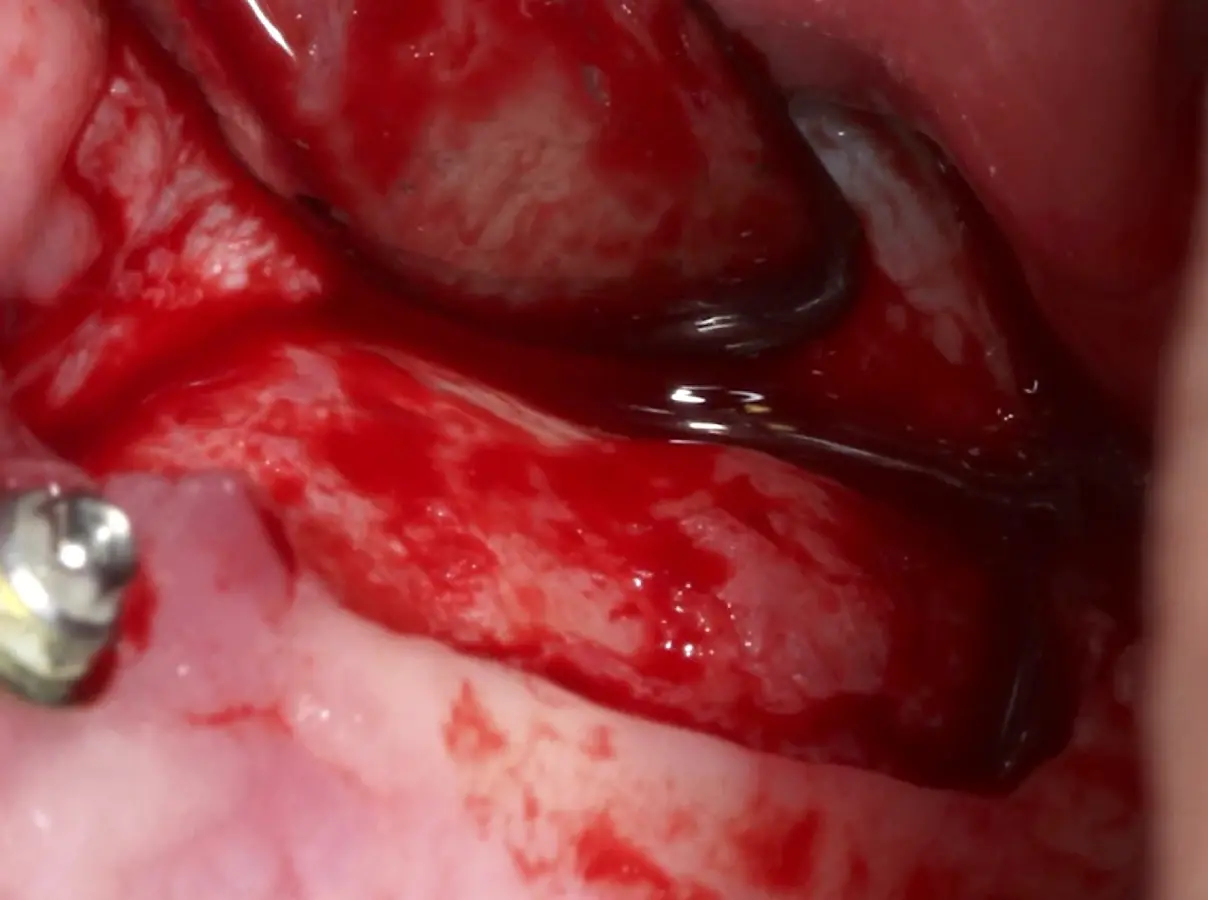

La técnica se inicia con la colocación de anestesia infiltrativa, posteriormente se realiza una incisión crestal o paracrestal con posibles liberantes verticales que deben de estar alejadas por lo menos 5 mm de los límites de la futura ventana y sobrepasar la línea mucogingival. Se realiza una elevación de colgajo, se inicia la antrostomía y antroplastía. Para ello, se emplea el inserto redondo diamantado de corte al momento de delimitar los bordes de la ventana de acceso. Luego se cambia al inserto aserrado liso de calibre fino con superficie diamantada, para profundizar y eliminar el hueso en el contorno de la ventana. Una vez que se traslucen los tejidos, se puede optar por el retiro de la tapa ósea o el levantamiento de ésta junto con la membrana.

El clínico puede retirar la tabla ósea o introducirla como “tienda de campaña” dentro del seno maxilar. En cualquiera de las alternativas, es importante evaluar la presencia de tabiques óseos y de la arteria postero alveolar superior.

Una vez elevado el piso sinusal según la planificación se realiza la evaluación clínica de la integridad de la membrana y de posibles desgarros a través de la maniobra de Valsalva.24 Consiste en pedir al paciente que respire profundamente y retenga el aire, cerrar la boca, apretar la nariz con los dedos y forzar la salida de aire. Al final de la prueba, es necesario mantener la presión entre 10 a 15 segundos. Se identificará la movilidad de la membrana y la ausencia de burbujas de aire para corroborar que no hay perforaciones. Dependiendo de la decisión clínica se puede optar por adicionar en la superficie de la membrana de Schneider membranas de colágeno o de plasma rico en fibrina (PRF) para dar mayor soporte durante la inserción del biomaterial de relleno óseo (Figura 10).